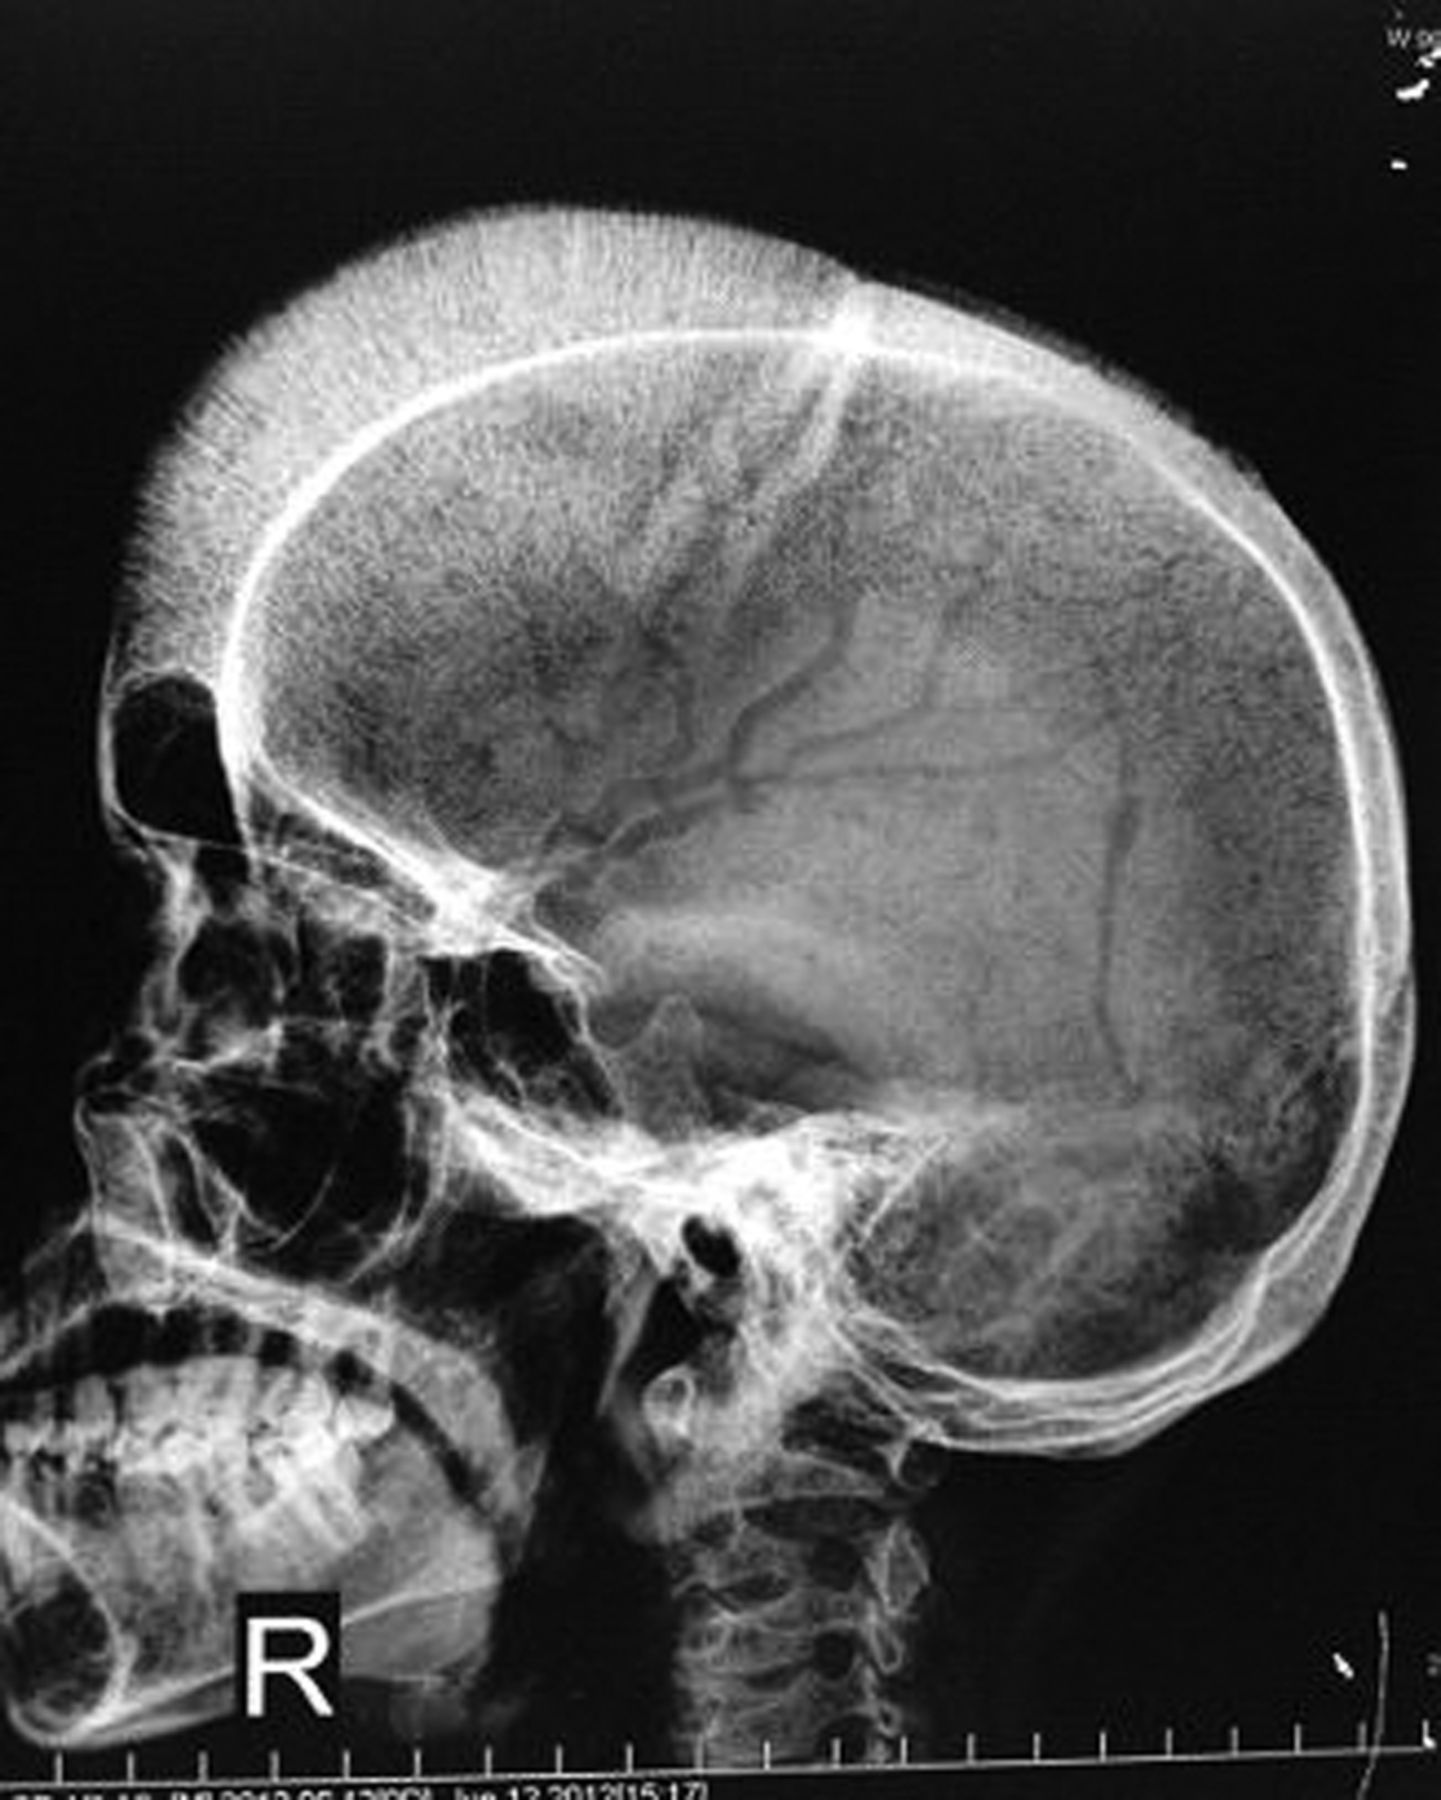

Hair on end sign is a radiographic finding. It is characterized by expansion of diploic space as a consequence of widening of trabeculae. Since these trabeculae are perpendicular to the skull vault, hence they appear as hair on the end of the skull. Hair on end sign is seen in the case of: - Thalassemia major - Iron deficiency anemia - Sickle cell disease - Hereditary spherocytosis - Neuroblastoma Reference: https://radiopaedia.org/articles/hair-on-end-sign-mnemonic#:~:text=The%20hair%20on%20end%20sign,hyperplasia%20along%20with%20skull%20vault. Image via: https://casereports.bmj.com/content/2013/bcr-2012-008095